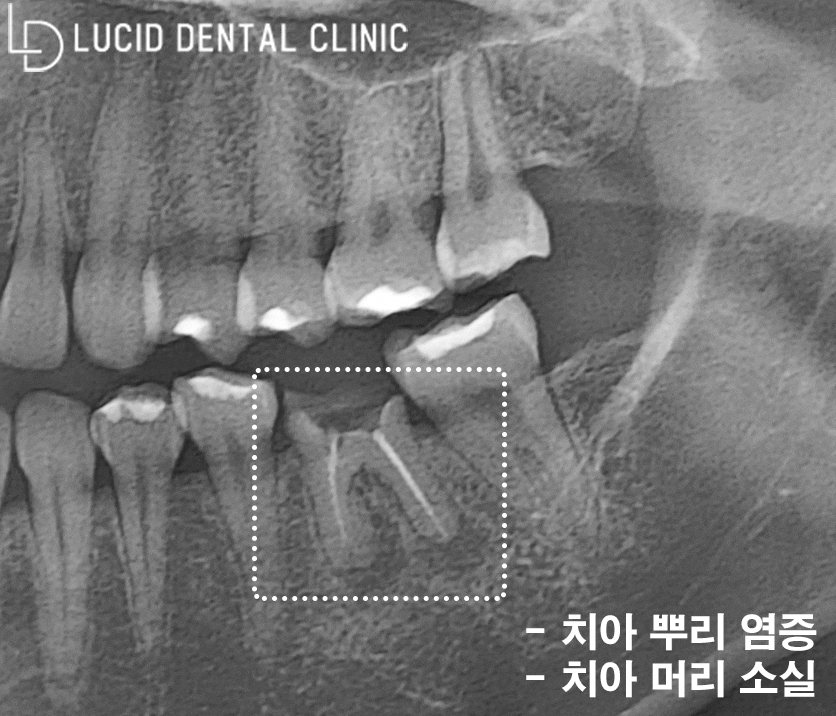

그럼 반대편 상황도 한 번 살펴볼까요?

다행히 치아 정출이 나타나진 않았지만

치아 뿌리 주변에 염증이 자리 잡고 있었고,

치아 머리 즉, 치관 소실이 일어났습니다.

이로 인해 치아 통증이 나타난 것으로 보입니다.

양쪽 치아가 모두 문제를 일으키고 있으니,

얼마나 불편하셨을지 상상조차 가지 않네요...